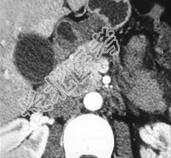

- 单项选择题女,56岁, 腹部胀痛不适、食欲减退,影像表现如下图, 最佳诊断是 ( )

A、胰腺转移癌

B、胰腺腺癌

C、胰腺假性囊肿

D、慢性胰腺炎

E、急性胰腺炎